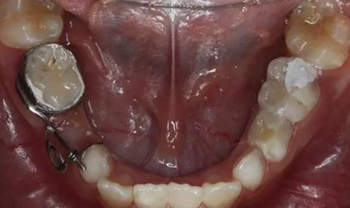

40、加力后,重新就位合面觀

41、加力就位后測力值200~250克,初級力值偏大,隨著力的衰減力值維持在100~150g左右,直至間隙推開后,力值逐漸遞減為零,作為間隙保持器使用,等待恒牙萌出

42、牙面拋光,試合制作好的間隙恢復器,將曲簧水平部分形成與牙面弧形一致,羧酸鋅水門汀粘結固定

43、粘結后的頰面觀

44、8周后復診間隙推開,自動變換為間隙保持器